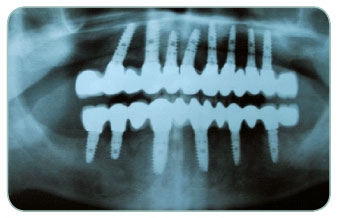

Our patient had lost all of her teeth a long time ago and was using unfixed crowns. She was not happy to clean her crowns every evening and she was missing to eat an apple. We have applied six Implants per upper and lower mouth and she is able to eat whatever she wants now. Total treatment period was only three months!